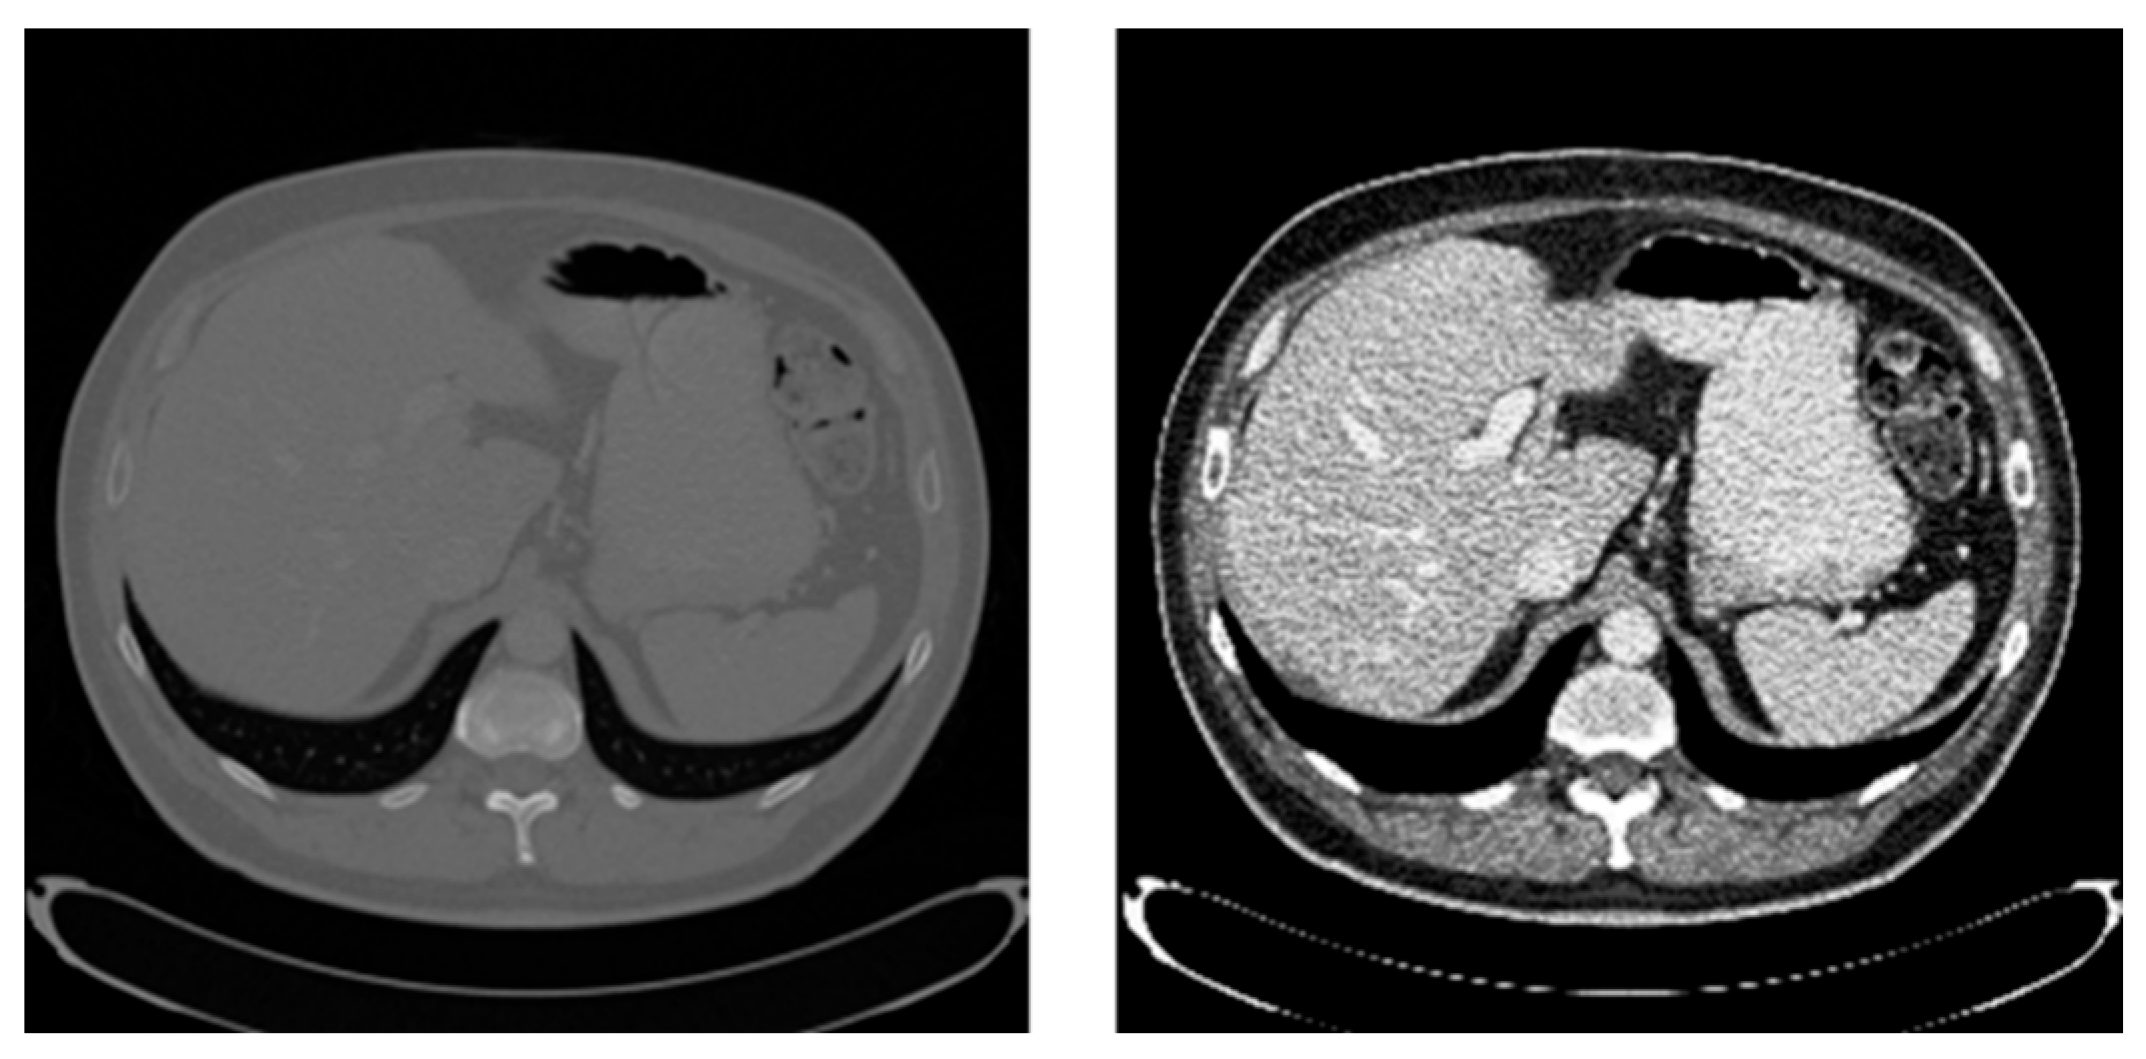

4.1. Dataset and Experimental Environment

4.1.1. LiTS2017 Dataset

4.1.2. Sliver07 Dataset

4.3. Image Preprocessing